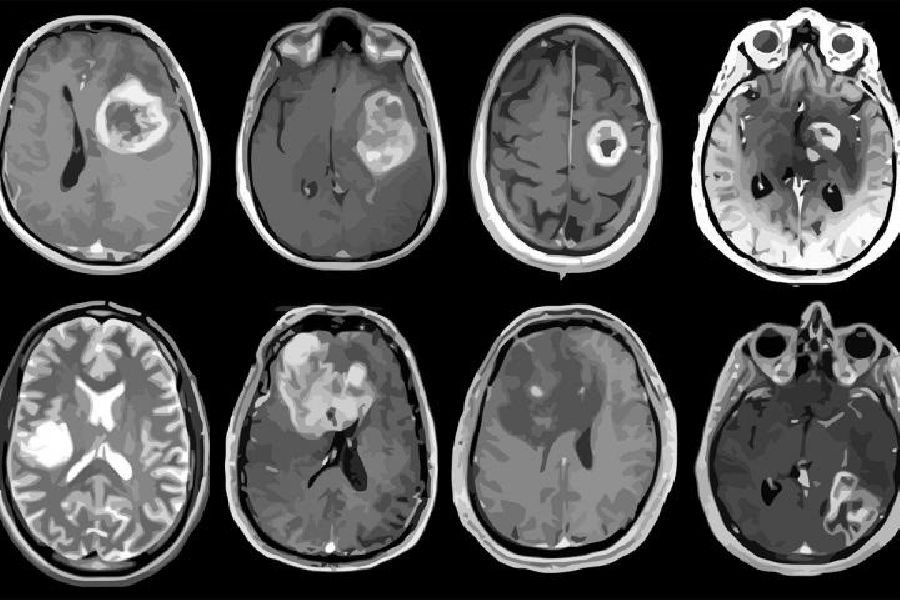

Descubierto nuevo objetivo de inmunoterapia para tumores cerebrales malignos

Los científicos señalan que la molécula, llamada CD161, es un receptor inhibidor que encontraron en las células T aisladas de muestras frescas de tumores cerebrales llamados gliomas difusos. Los gliomas incluyen el glioblastoma, el tipo de tumor cerebral más agresivo e incurable. El receptor CD161 es activado por una molécula llamada CLEC2D en células tumorales y células inmunodepresoras en el cerebro, según los investigadores. La activación de CD161 debilita la respuesta de las células T contra las células tumorales.